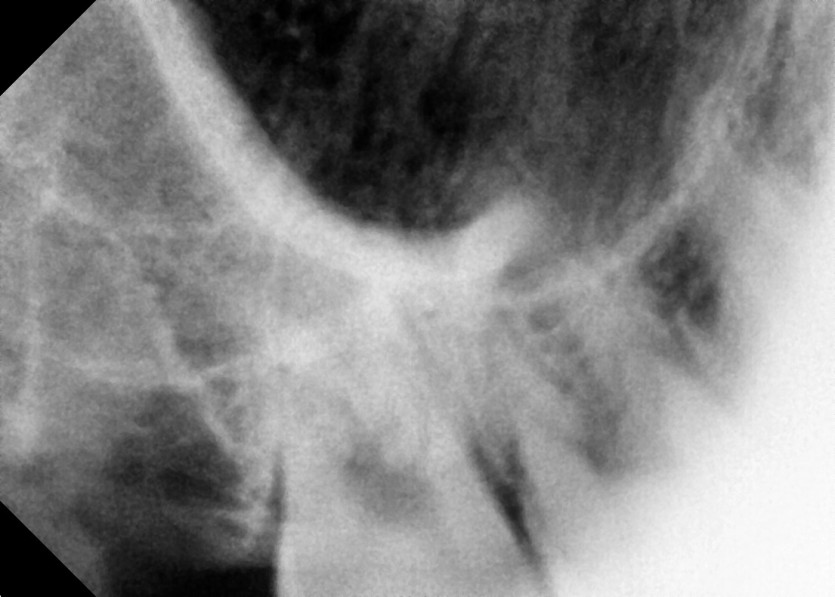

#18,28,38,48 사랑니 발치

구강 외과 전문의가 당일 발치했습니다.